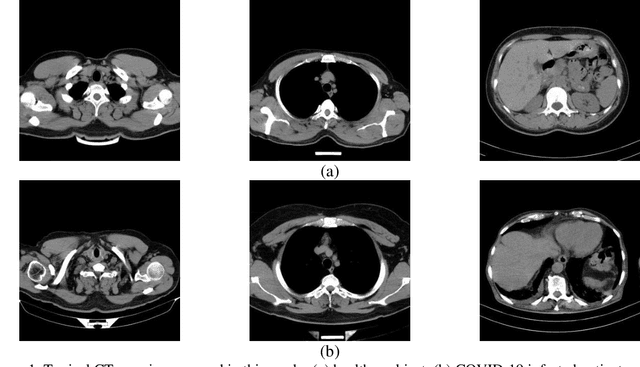

Abstract:The new coronavirus has caused more than 1 million deaths and continues to spread rapidly. This virus targets the lungs, causing respiratory distress which can be mild or severe. The X-ray or computed tomography (CT) images of lungs can reveal whether the patient is infected with COVID-19 or not. Many researchers are trying to improve COVID-19 detection using artificial intelligence. In this paper, relying on Generative Adversarial Networks (GAN), we propose a Semi-supervised Classification using Limited Labelled Data (SCLLD) for automated COVID-19 detection. Our motivation is to develop learning method which can cope with scenarios that preparing labelled data is time consuming or expensive. We further improved the detection accuracy of the proposed method by applying Sobel edge detection. The GAN discriminator output is a probability value which is used for classification in this work. The proposed system is trained using 10,000 CT scans collected from Omid hospital. Also, we validate our system using the public dataset. The proposed method is compared with other state of the art supervised methods such as Gaussian processes. To the best of our knowledge, this is the first time a COVID-19 semi-supervised detection method is presented. Our method is capable of learning from a mixture of limited labelled and unlabelled data where supervised learners fail due to lack of sufficient amount of labelled data. Our semi-supervised training method significantly outperforms the supervised training of Convolutional Neural Network (CNN) in case labelled training data is scarce. Our method has achieved an accuracy of 99.60%, sensitivity of 99.39%, and specificity of 99.80% where CNN (trained supervised) has achieved an accuracy of 69.87%, sensitivity of 94%, and specificity of 46.40%.